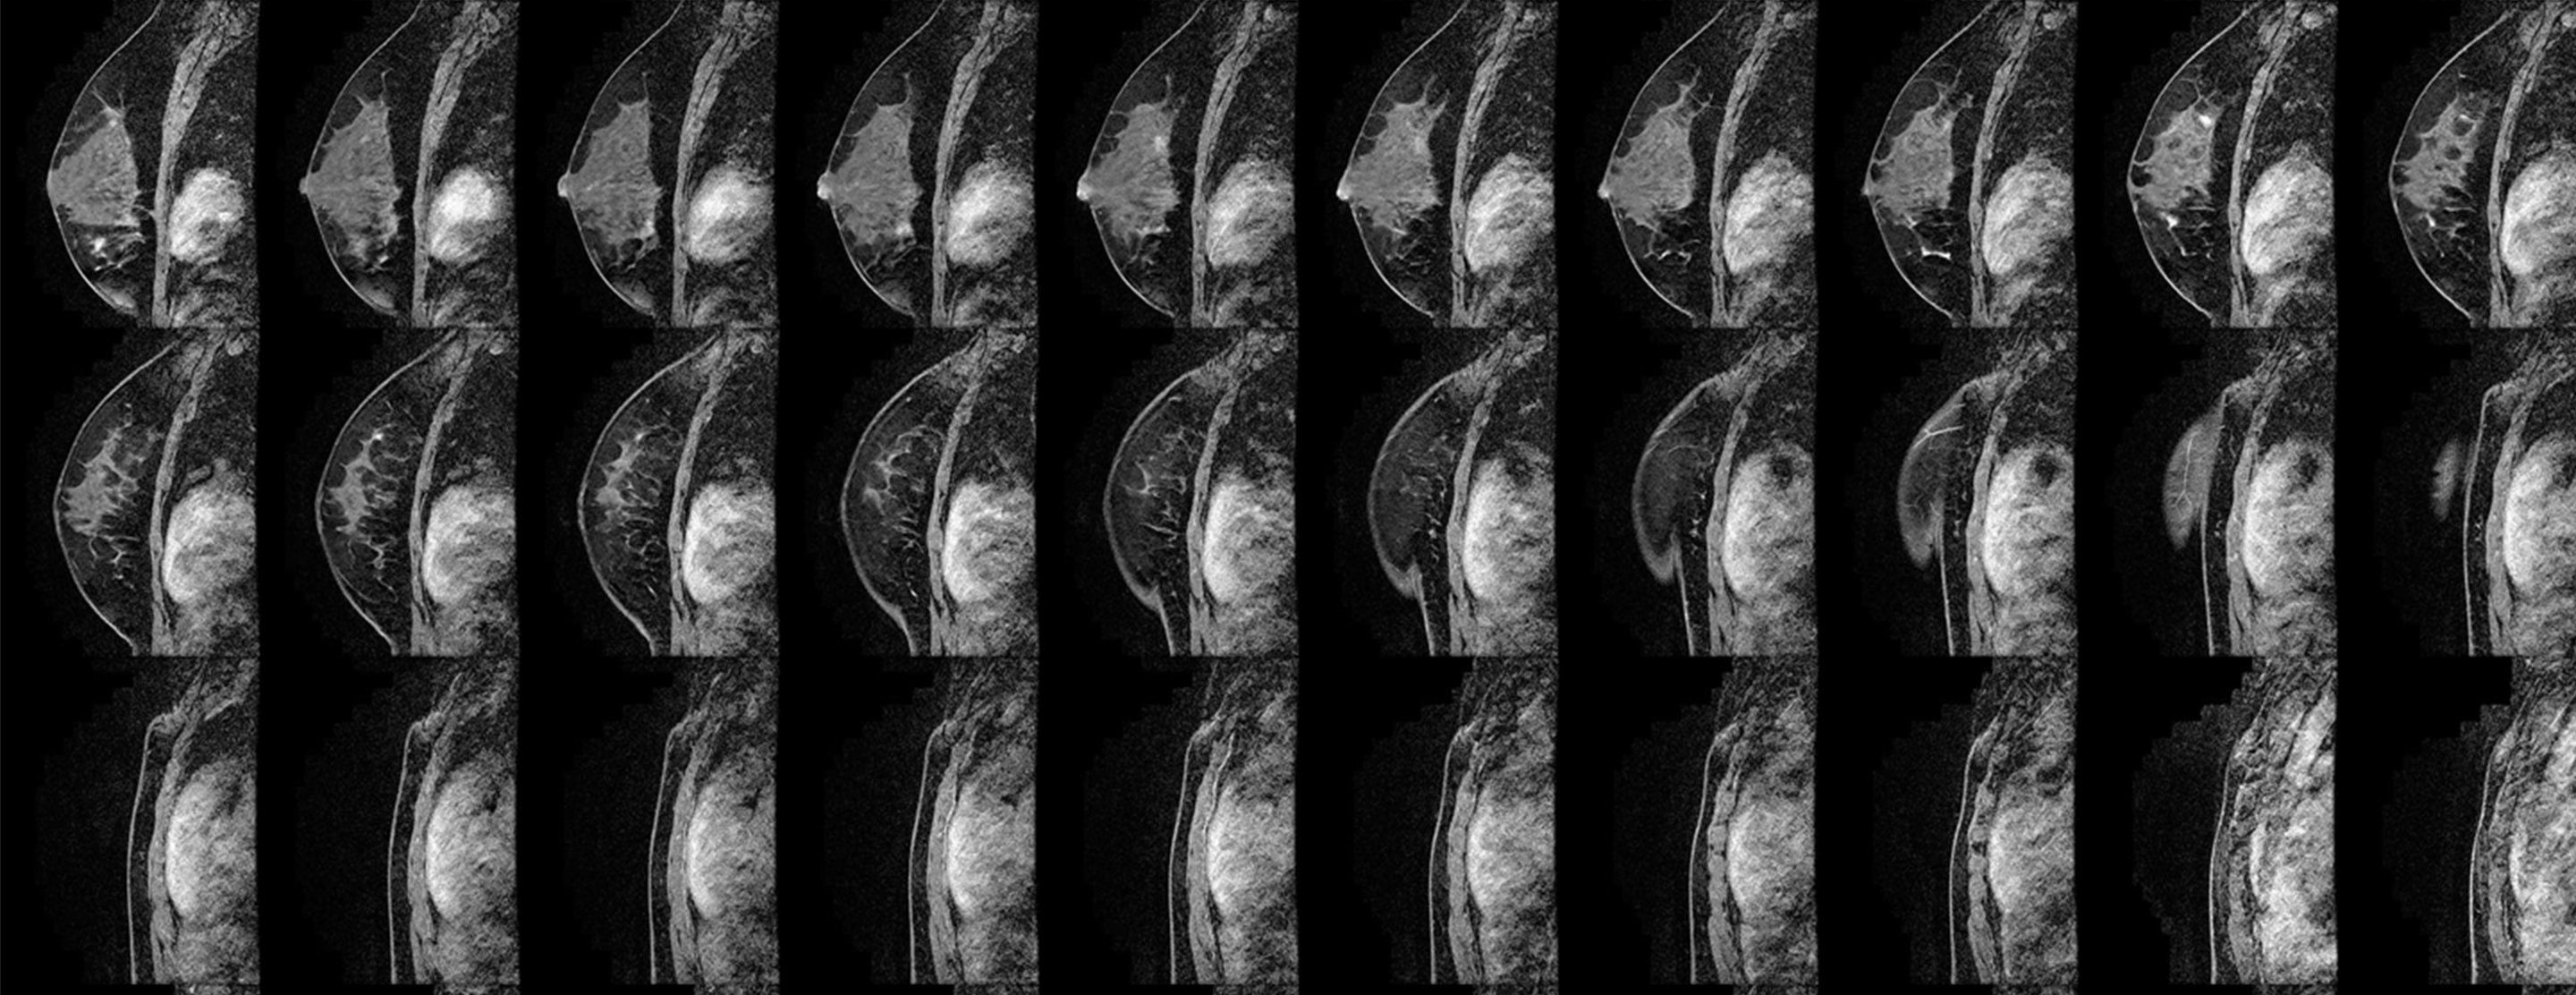

You stay awake during the procedure, lying facedown on a padded MRI scanner table that has a cushioned opening for your breast. The opening is surrounded by a device called a breast coil that holds the breast in place and works with the machine to create images. The MRI technologist takes images for five to 10 minutes to precisely locate the abnormality. You need to remain very still during this part of the procedure.